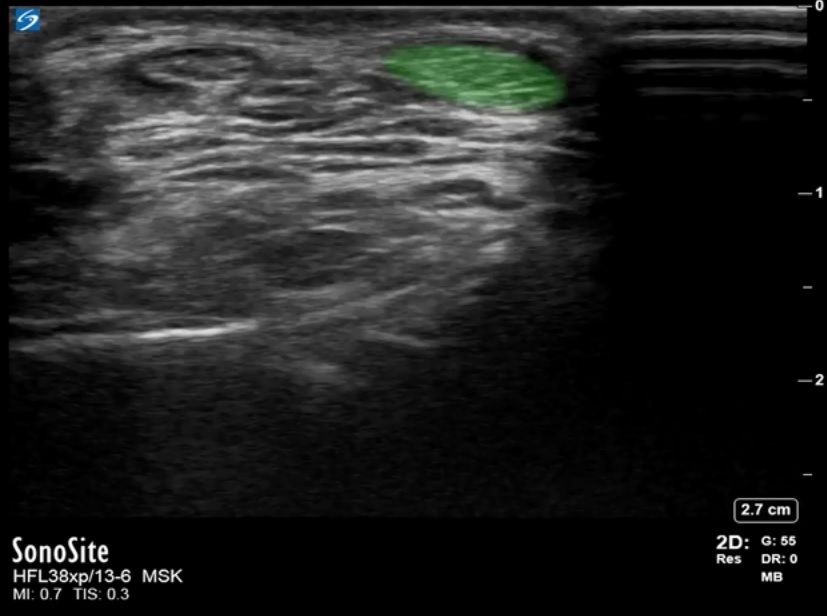

Foot & Ankle Anterior Recess Tibialis Anterior Image

Highlighted Area: Tibialis Anterior Tendon